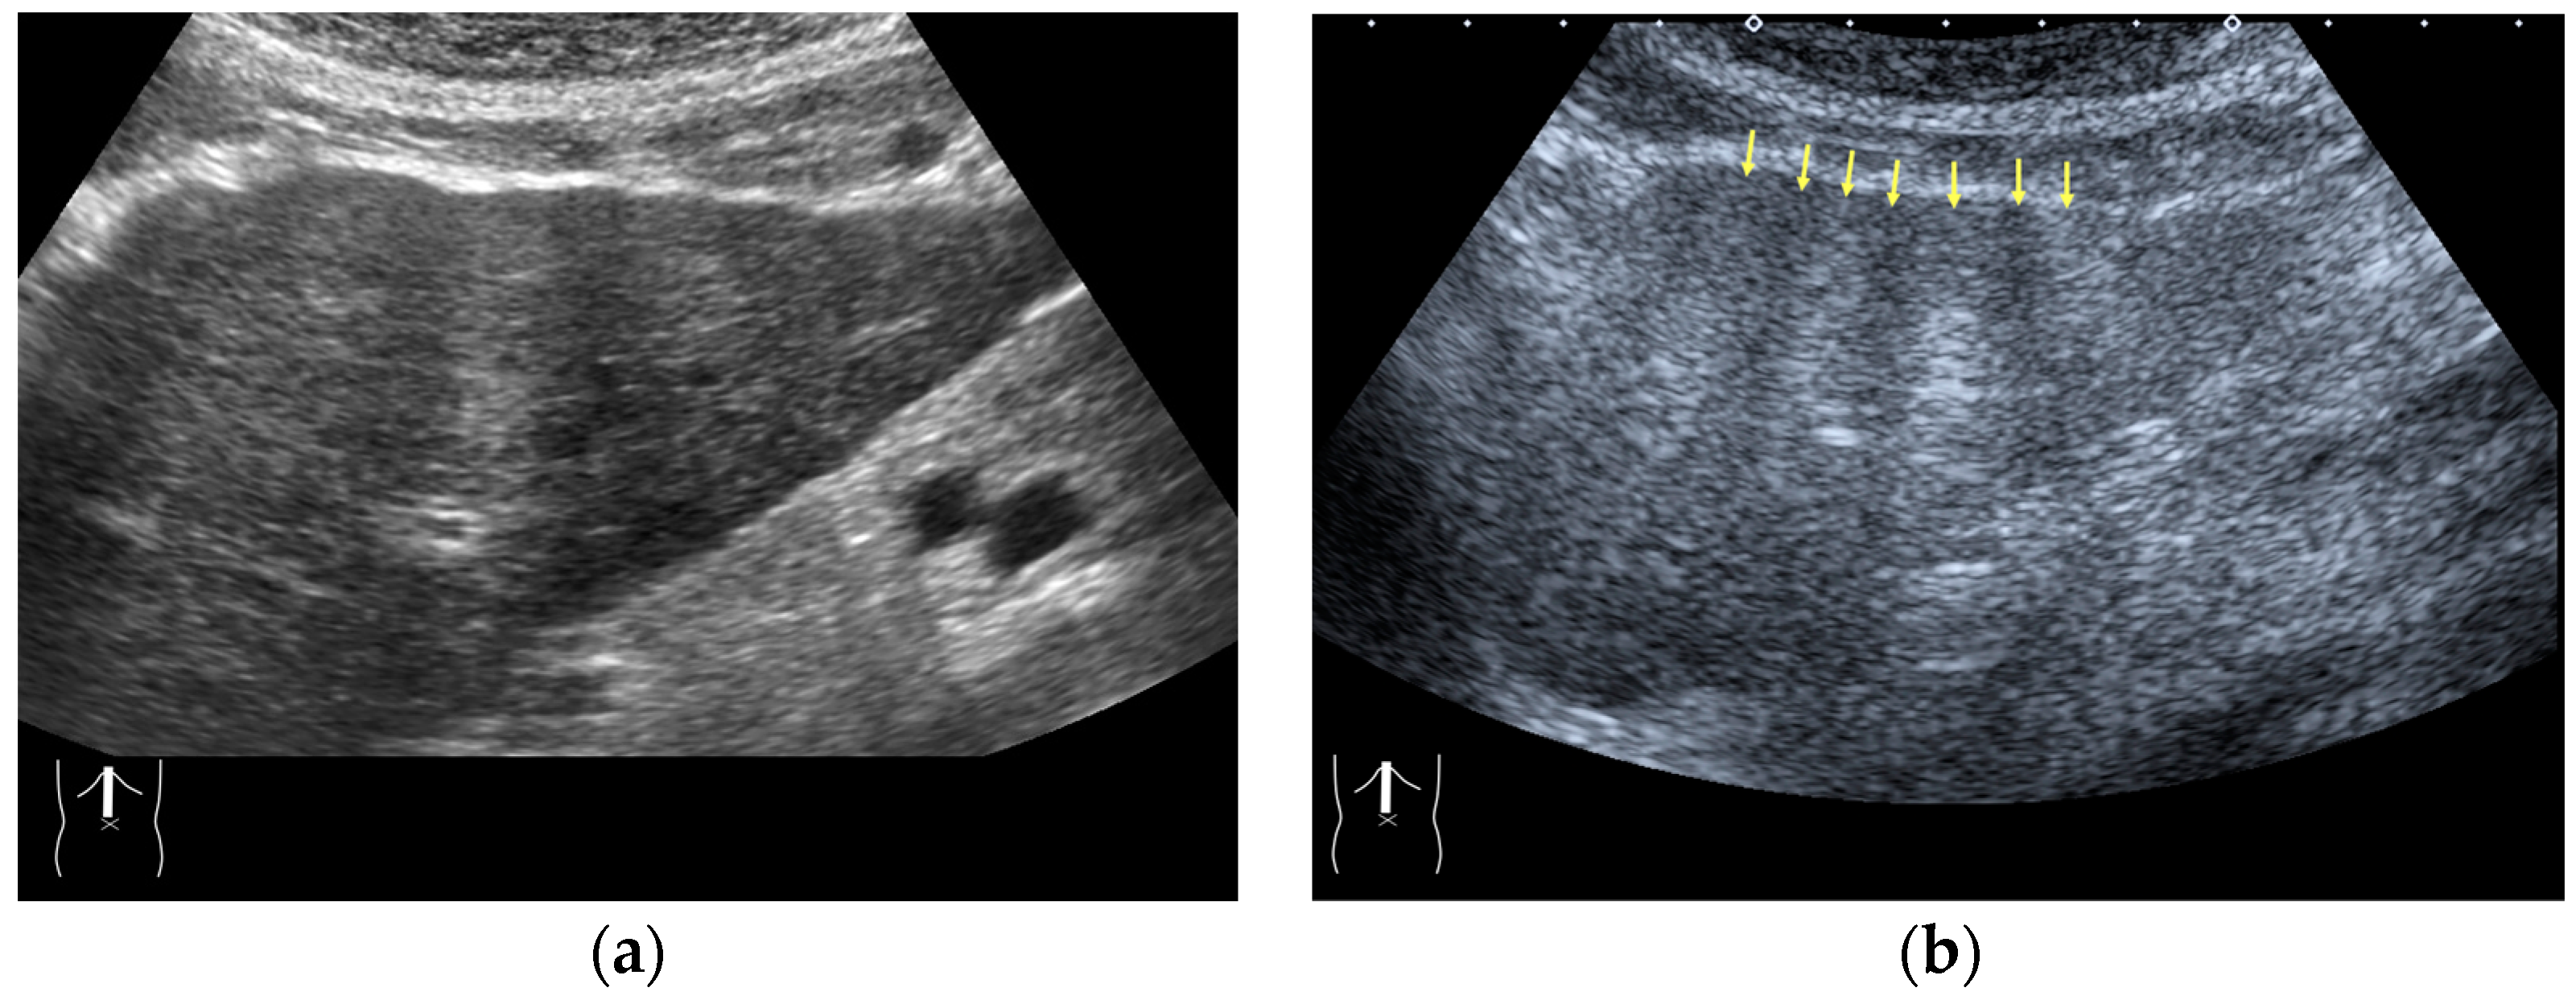

There are two sources of sound attenuation in the human body, (a) reflection and sound scattering and (b) sound absorption [47]. Both factors contribute to the formation of attenuation artifacts. These artifacts mainly occur in difficult patients (e.g., patients with advanced liver cirrhosis, patients with obesity, and patients with severe fatty liver) [48,49,50]. Increasing the mechanical index (M.I.) is not recommended for overcoming this attenuation artifact because an excessively increased M.I. causes visible microbubble destruction at the hepatic surface. Generally speaking, US attenuation in soft tissues is highly dependent on the US frequency and is nearly proportional to it (Figure 6). Less attenuation with a lower frequency results in an increased penetration depth. Thus, the most useful strategy is to use a transducer with a lower transmission frequency at the expense of a slightly deteriorated image quality (Figure 7). Another diagnostic strategy is to adjust the STC 3), which slightly improves the visualization of deep areas (Figure 8). We present herein a representative case of a “pseudo-tumor” in a decompensated cirrhotic patient where less attenuated US beams passing through the ascites mimicked an echogenic tumor at the periphery of the liver not only in B-mode US but also in CEUS (Figure 9).

Figure 9.

Representative case of a sound attenuation artifact. The presence of massive ascites leads to US beams passing through less attenuated ascites, mimicking an echogenic liver tumor (arrows). (a) B-mode US and (b) CEUS.